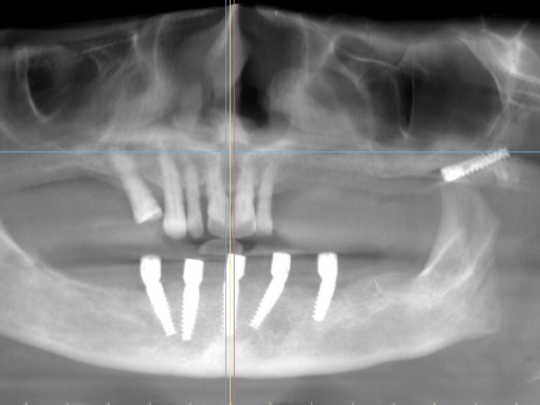

Implant

Before and After